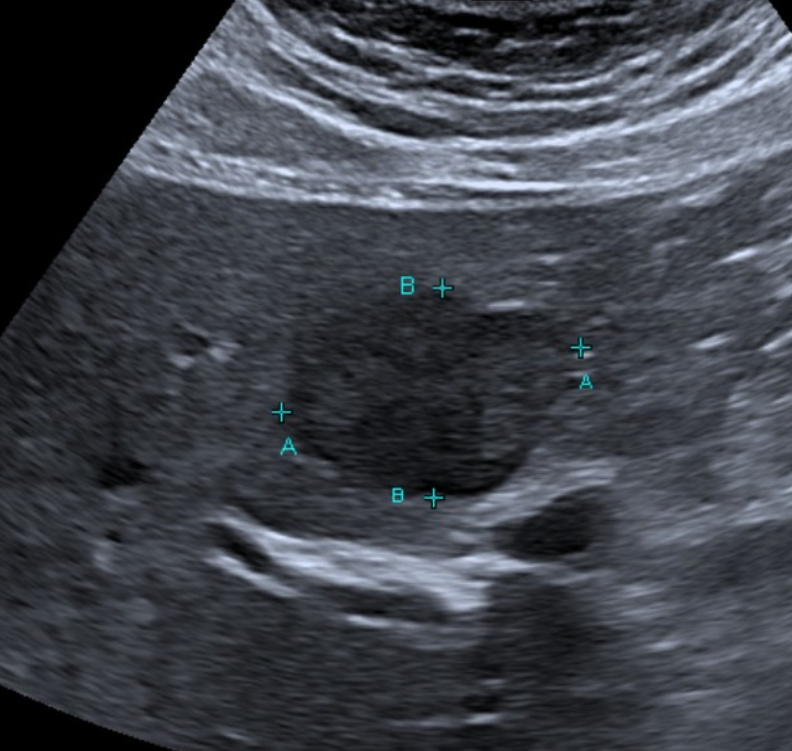

Which of these liver masses/nodules is a malignant tumor.

B-mode ultrasonography is highly sensitive for detecting focal liver lesions but is poorly specific for lesion type. Hepatic masses may appear:

• Hypoechoic, hyperechoic, or mixed echogenicity

• Well-marginated or irregular

• Solitary or multifocal

Importantly, echogenicity does not correlate reliably with malignancy. Multiple studies have demonstrated substantial overlap in the sonographic appearance of benign nodules, primary hepatic tumors, and metastatic lesions (Nyland et al., 2002; O’Brien et al., 2004)

In a large retrospective study of canine liver tumors, no consistent B-mode ultrasonographic features reliably differentiated hepatocellular carcinoma, cholangiocarcinoma, sarcoma, or metastatic lesions, aside from lesion distribution (O’Brien et al., 2004). Hepatocellular carcinomas were more likely to be solitary, whereas sarcomas and metastases were more often multifocal, but significant overlap existed.

Given the substantial overlap in ultrasonographic appearance across lesion types, tissue sampling is essential in most cases

Ultimately, histopathology remains the gold standard for differentiating benign hyperplasia, primary neoplasia, and metastatic disease (Cullen & Stalker, 2016).